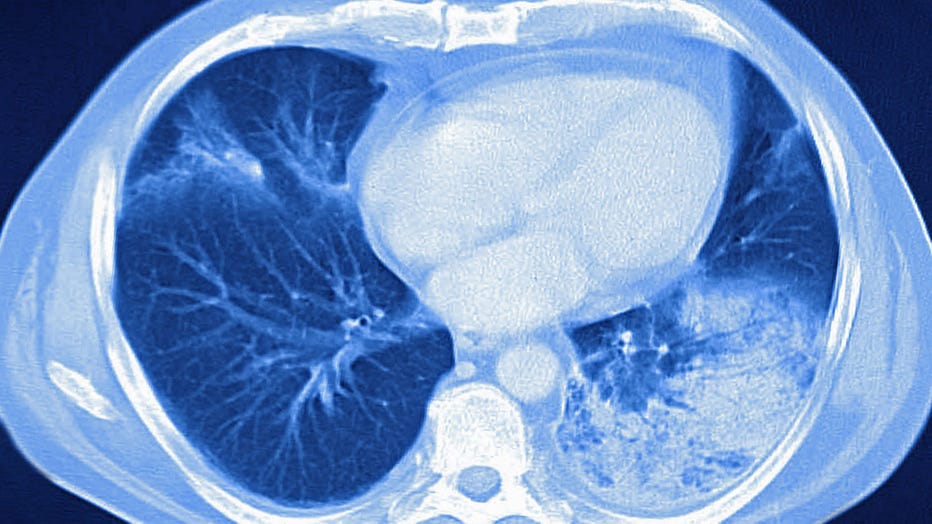

Acute pneumonia, seen on a cross-section thoracic CT-scan. (Photo by: BSIP/Universal Images Group via Getty Images)

Dr. Sarah Park, medical director of medical affairs at Karius, a California biotech company, told Fox News Digital the term "white lung syndrome" refers to some pneumonia-infected chest scans that show "diffusely damaged lungs."